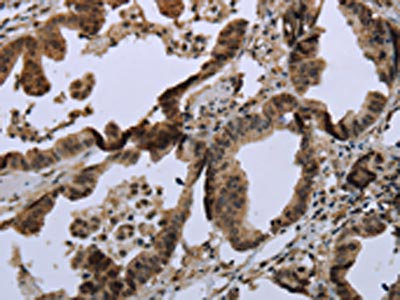

The image on the left is immunohistochemistry of paraffin-embedded Human liver cancer tissue using CSB-PA557048(MAPKAPK2 Antibody) at dilution 1/20, on the right is treated with synthetic peptide. (Original magnification: ×200)

The image on the left is immunohistochemistry of paraffin-embedded Human colon cancer tissue using CSB-PA557048(MAPKAPK2 Antibody) at dilution 1/20, on the right is treated with synthetic peptide. (Original magnification: ×200)